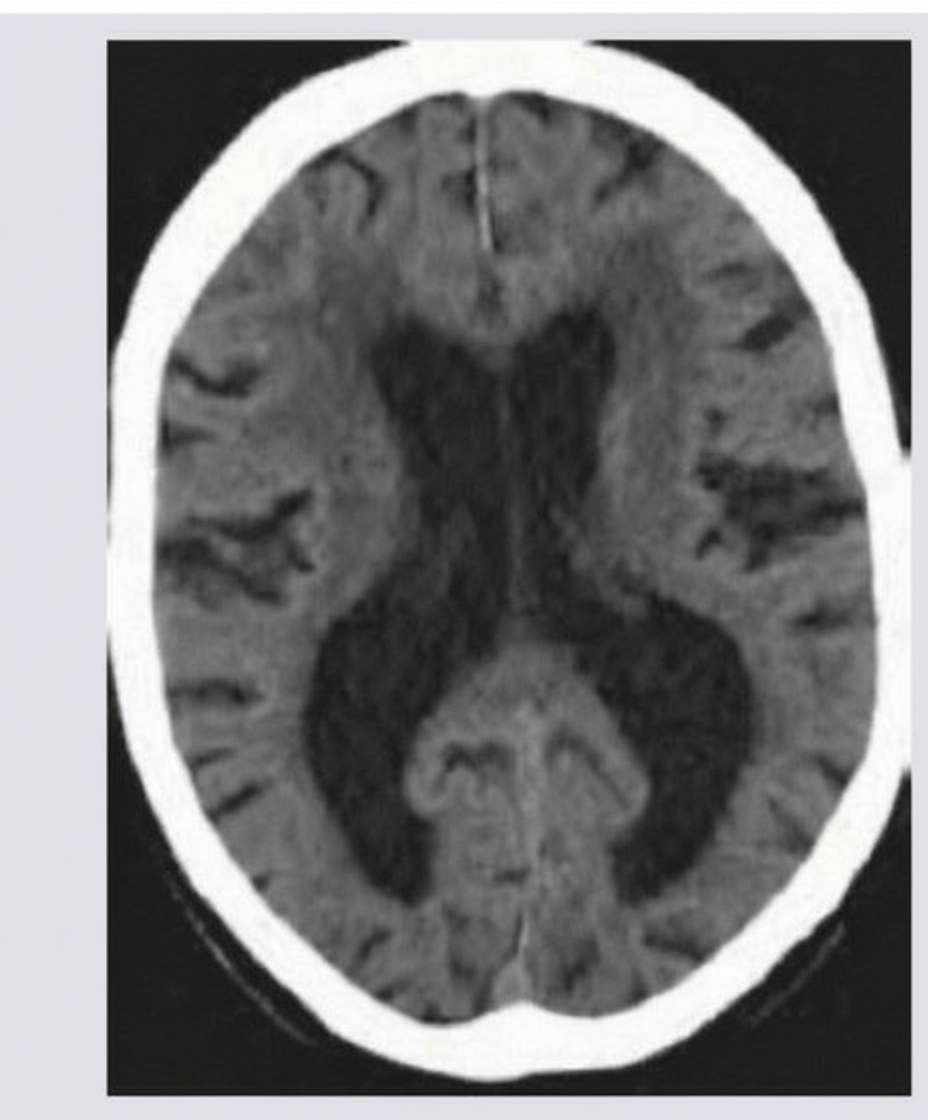

An 88-year-old man is brought to his primary care physician by his son. The patient has been in excellent health his entire life, but in the last few years appears to have grown steadily confused. He frequently calls his son about things that they have already discussed, forgets where he has placed his keys, and recently the patient's son noticed several unpaid bills on the patient's desk at home. The patient is upset at being "dragged" into see the physician and claims that everything is fine--he is just "getting older". A complete neurologic exam is normal except for significant difficulty with recall tasks. In the course of the medical work-up, you obtain a CT scan and see the findings in figure A. What is the most likely cause of this patient's CT findings?